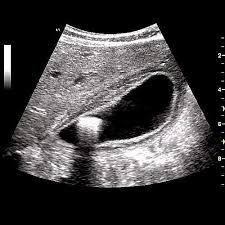

Idea Of Echographie de la thyroide PDF